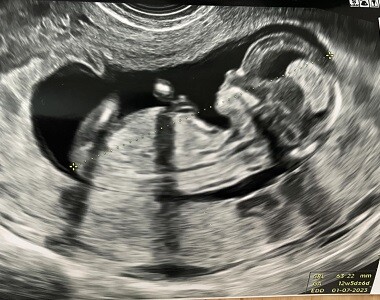

Koncem týdne jsme taky vyrazili na kontrolu do těhotenské poradny. Překvapilo mě, že mě nikdo nenutil do žádných nepříjemných vyšetření, proběhl pouze ultrazvuk. Dle všeho se zatím Liborkovi daří dobře. Hlavička se mu bohužel nesmrskla, což mě přivádí do stavu mírného šílenství, zato váhový odhad se příliš nezměnil a stále se zdá, že bude o něco menší, než byla Agátka.